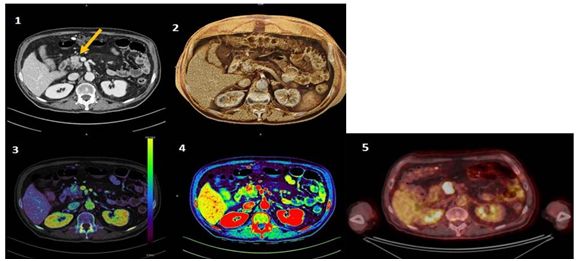

Pancreas head injury was also visualized on PET-CT and confirmed as squamous cell carcinoma with biopsy. In the iodine map, we can observe with greater definition the lesion with the attenuation of the amount of iodine, which is even more evident in monoenergetic 40 keV and we visualize it texturally by cinematic rendering, as showed in Figure 1. Quantitative analysis revealed increased Iodine enhancement (carcinoma: 5.0mg/ml; 76.8% versus normal tissue: 2.9 mg/ml; 44.7%), as well as Fat Fraction (carcinoma: 18.3% versus normal tissue: 8.9%) and greater standard deviation, what may represent greater heterogeneity of analyzed tissue when compared to the normal tissue (Figure 2).

Figure 2 Quantitative analysis of the lesion in iodine map: with a normalized ROI in Descendent Aorta and two ROIs for evaluation of carcinoma lesion and normal tissue of Pancreas, showing increased Iodine enhancement as well as Fat Fraction and greater standard deviation, when compared to the normal tissue. Show an irregular, heterogeneously enhanced lesion (arrows) in the head of the pancreas, with an iodine uptake of 5.0 mg/mL, which is almost double that in the adjacent normal pancreatic tissues (2.9 mg/mL).